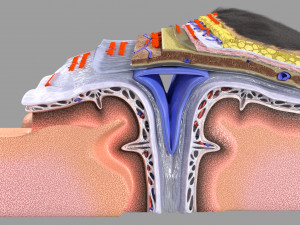

Brain with meninges scalp detailed labelled 3D 3D मॉडल

A blend model of brain along with its covering layers (meninges), skull bone and scalp labelled in detail and anatomically precise. The parts depicted are white, gray, pia, arachnoid, dura, bone, skin, fat, aponeurosis, periosteum, falx cerebri and more.

The material is high resolution image textures and normal maps based on non overlapping UVs. The texture and normal maps are packed with the blend file itself.